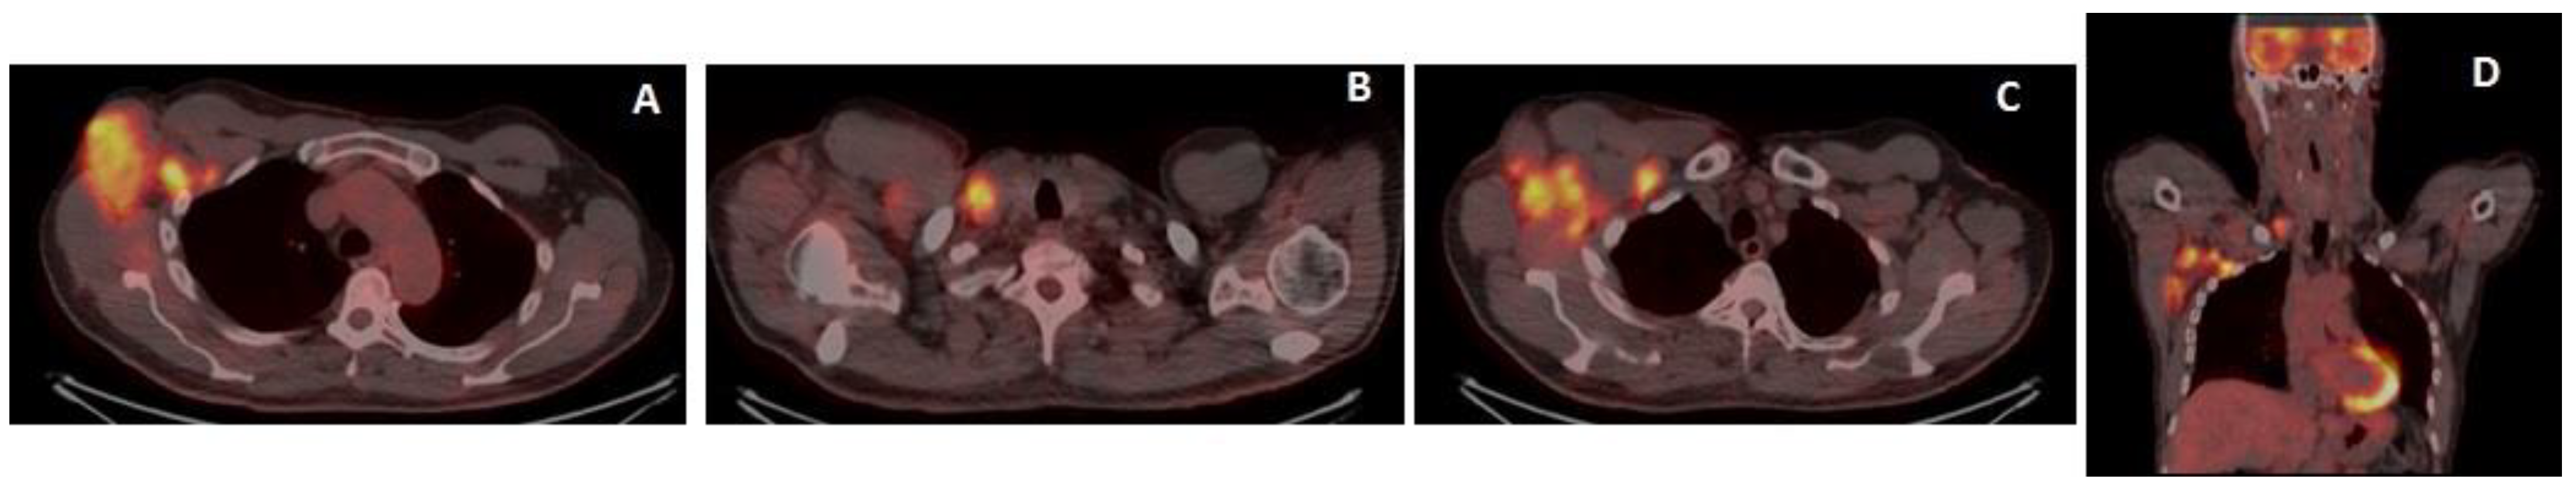

Cavanna, L.; Grassi, S.O.; Ruffini, L.; Michieletti, E.; Carella, E.; Palli, D.; Zangrandi, A.; Inzerilli, N.; Bernuzzi, P.; Di Nunzio, C.; et al. Non-Hodgkin Lymphoma Developed Shortly after mRNA COVID-19 Vaccination: Report of a Case and Review of the Literature. Medicina 2023, 59, 157. https://doi.org/10.3390/medicina59010157